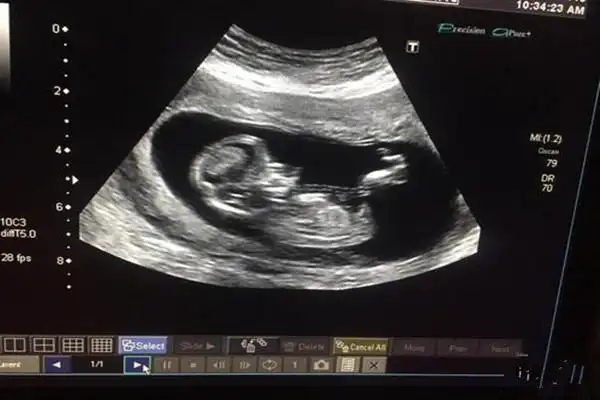

这是男宝还是女宝 ,昨天做的nt咱也不敢问医生

如果nt图是弯着的生男孩,nt图是平行的生女孩